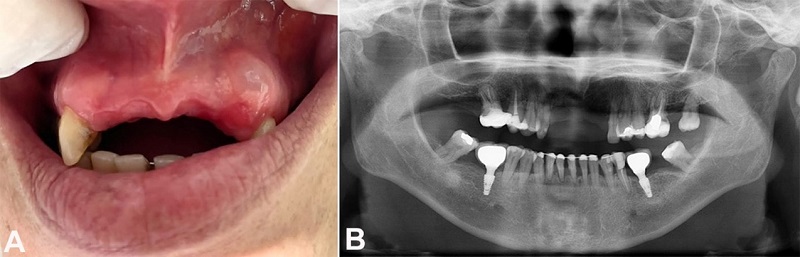

This case report was conducted based on the CARE guidelines for case reports.7 A 52-year-old female patient presented to the dentist complaining of a gingival lesion over the last 3 months. The patient denied a history of local trauma. The oral examination revealed an asymptomatic translucent nodule in the upper left gingiva, near tooth #11, measuring approximately 6mm, absent anterior teeth, and generalized gingival resorption (Figure 1A). There were no imaging changes (Figure 1B).